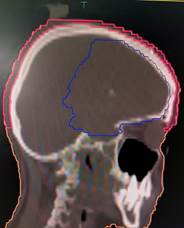

to the level of the foramen magnum (6) as depicted in Figure 1 given below.

Figure 1. shows scalp contours in axial, coronal,

and sagittal planes.